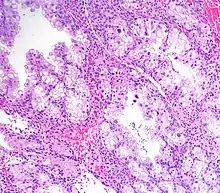

Micrograph showing Arias-Stella reaction in endometrium

Arias-Stella reaction is due to progesterone primarily. Cytologically, it looks like a malignancy and, historically, it was diagnosed as endometrial cancer.[1]

It is characterized by nuclear enlargement and may also have any of the following: an irregular nuclear membrane, granular chromatin, centronuclear vacuolization, and pseudonuclear inclusions.[1]